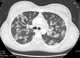

Varicella pneumonia

Chickenpox, also known as varicella, is a highly contagious disease caused by the initial infection with varicella zoster virus (VZV). The disease results in a characteristic skin rash that forms small, itchy blisters, which eventually scab over. [Source: Wikipedia ]